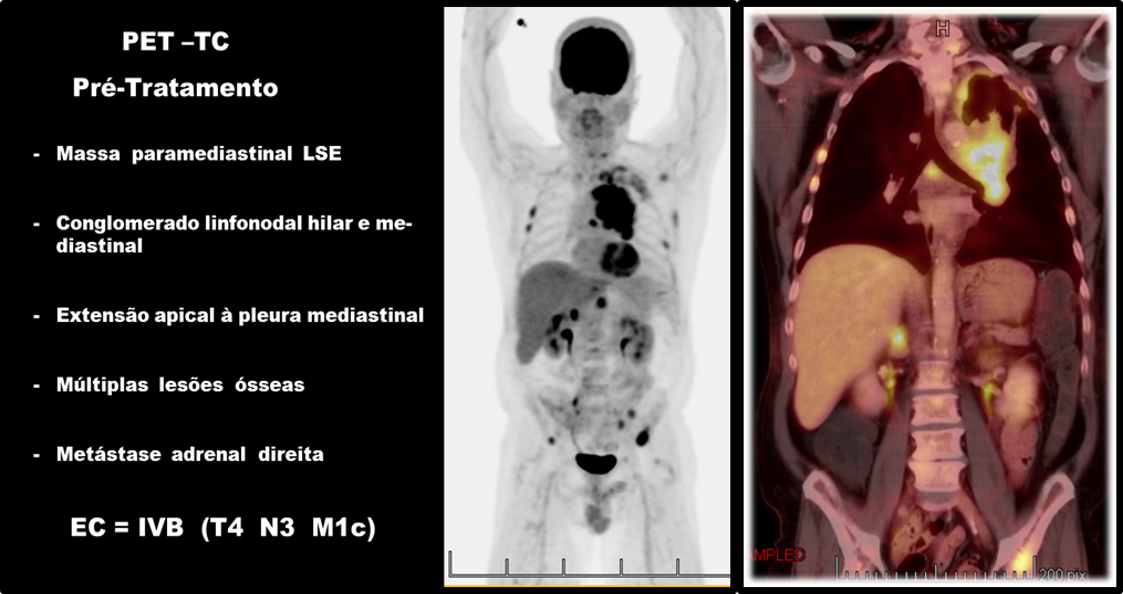

Nosso paciente preenche critérios da UICC para EC IVB (T4 N3 M1c) ou DE pelo VALSG.